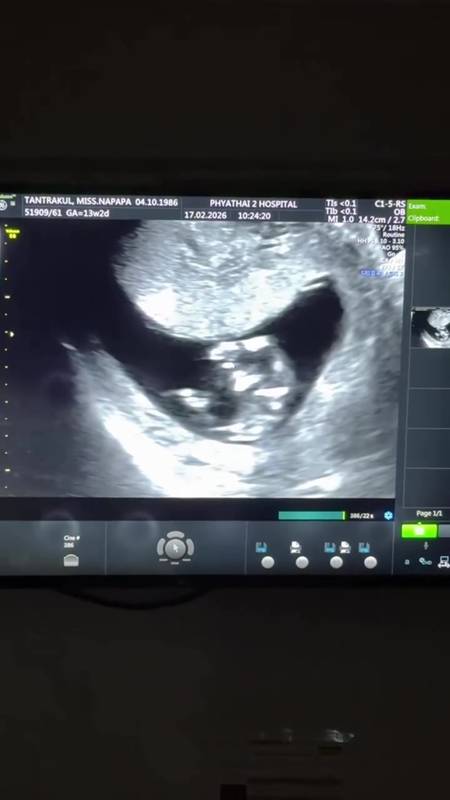

แพท ณปภา ประกาศข่าวดีตั้งท้องลูกคนที่สองแล้ว ขึ้นแท่นคุณแม่ลูก 2 - พี ชานนท์ ยิ้มแก้มปริเตรียมเป็นคุณพ่อ หลังจากที่ก่อนหน้านี้นักแสดงสาว แพท ณปภา และสามี พี ชานนท์ ออกมาเปิดเผยว่ากำลังตั้งใจมีลูกคนที่ 2 ซึ่งก่อนหน้านี้แม้จะเจอกับข่าวเศร้าเรื่อท้องลม แต่ทั้งคู่ก็ไม่เคยท้อ และล่าสุด (17 กุมภาพันธ์ 2569) แพท ณปภา และ พี ชานนท์ ก็ได้ออกมาประกาศข่าวดีที่หลายคนรอคอยว่าได้ตั้งท้องลูกคนที่ 2 ขณะนี้อายุครรภ์ได้ 3 เดือน ขึ้นแท่นเป็นคุณแม่ลูก 2 และคุณพ่อมือใหม่ป้ายแดงเป็นที่เรียบร้อยแล้ว โดย แพท และ พี ได้ออกมาประกาศผ่านคลิปในอินสตาแกรม พร้อมเผยภาพอัลตร้าซาวด์ลูกน้อยในท้อง และแคปชั่นว่า "#คุณแม่ลูก2เรา2 คนมีข่าวดีมาบอก #คุณแม่ลูก2" ซึ่งก้มีทั้งดาราคนดังและแฟนคลับเข้าไปคอมเมนต์ร่วมแสดงความยินดีกันยกใหญ่